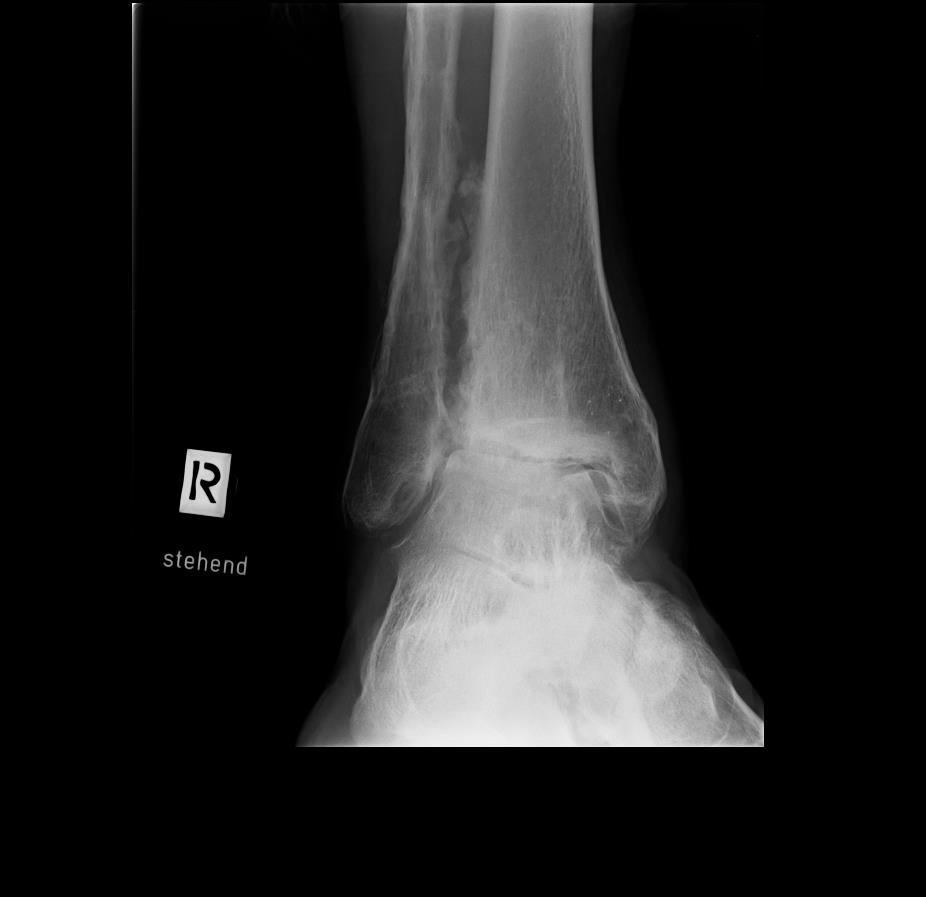

Mit einer Röntgenuntersuchung kann der Schweregrad der Arthrose festgestellt werden.

Die Arthrose des oberen Sprunggelenkes ist keine Alterserscheinung und betrifft häufig jüngere Patienten. Sie bildet sich zumeist in der Folge von Verletzungen (Knochenbrüche und alte Bandverletzungen), in deren Folge das Gelenk seine Stabilität einbüßt. Dies führt zum Verschleiß des Gelenks.

Häufig äußert sich die Arthrose des oberen Sprunggelenks in ihrer Anfangsphase mit einem „Anlaufschmerz“ im Fuß nach dem Aufstehen. Ist der Fuß eingelaufen, bessern sich die Beschwerden zunächst. Mit zunehmendem Verschleiß des Gelenkes kommt es aber zum Dauerschmerz. Längere Belastungen sind meist nicht mehr möglich.

Die typischen Beschwerden sind Schmerz, Schwellung und eine eingeschränkte Beweglichkeit. Das geschwollene Gelenk reagiert besonders empfindlich auf Druck. Die verminderte Beweglichkeit äußert sich häufig durch Probleme beim Treppensteigen. Abhängig von der Schwere der Arthrose stehen unterschiedliche Therapiekonzepte zur Verfügung.